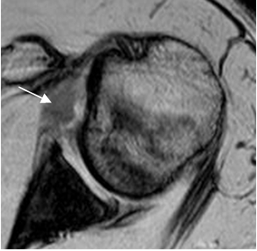

Pueden lesionarse los ligamentos glenohumerales superior, medio o inferior. (Fig 77 A y B).

Fig 77A. Engrosamiento del LGHM.

RM axial en GE. Engrosamiento del LGHM, por lesión residual.